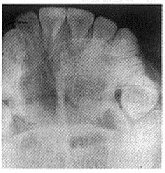

1、球上頜囊腫發生於上頜側切牙與尖牙之間,牙常被排擠而移位。X線片上顯示囊腫陰影在牙根之間,而不在根尖部位。牙無齲壞變色,牙髓均有活力。

2、本齶囊腫位於切牙管內或附近(來自切牙管殘餘上皮)。X線片上可見到切牙管擴大的囊腫陰影。

3、正中囊腫位於切牙孔之後,齶中縫的任何部位。X線片上可見縫間有圓形囊腫陰影。亦可發生於下頜正中線處。